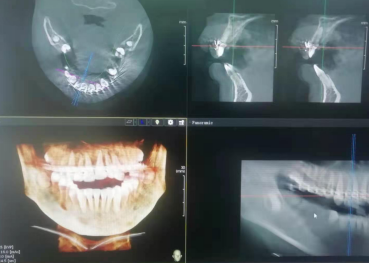

术后复诊CT

摘除固定板ct